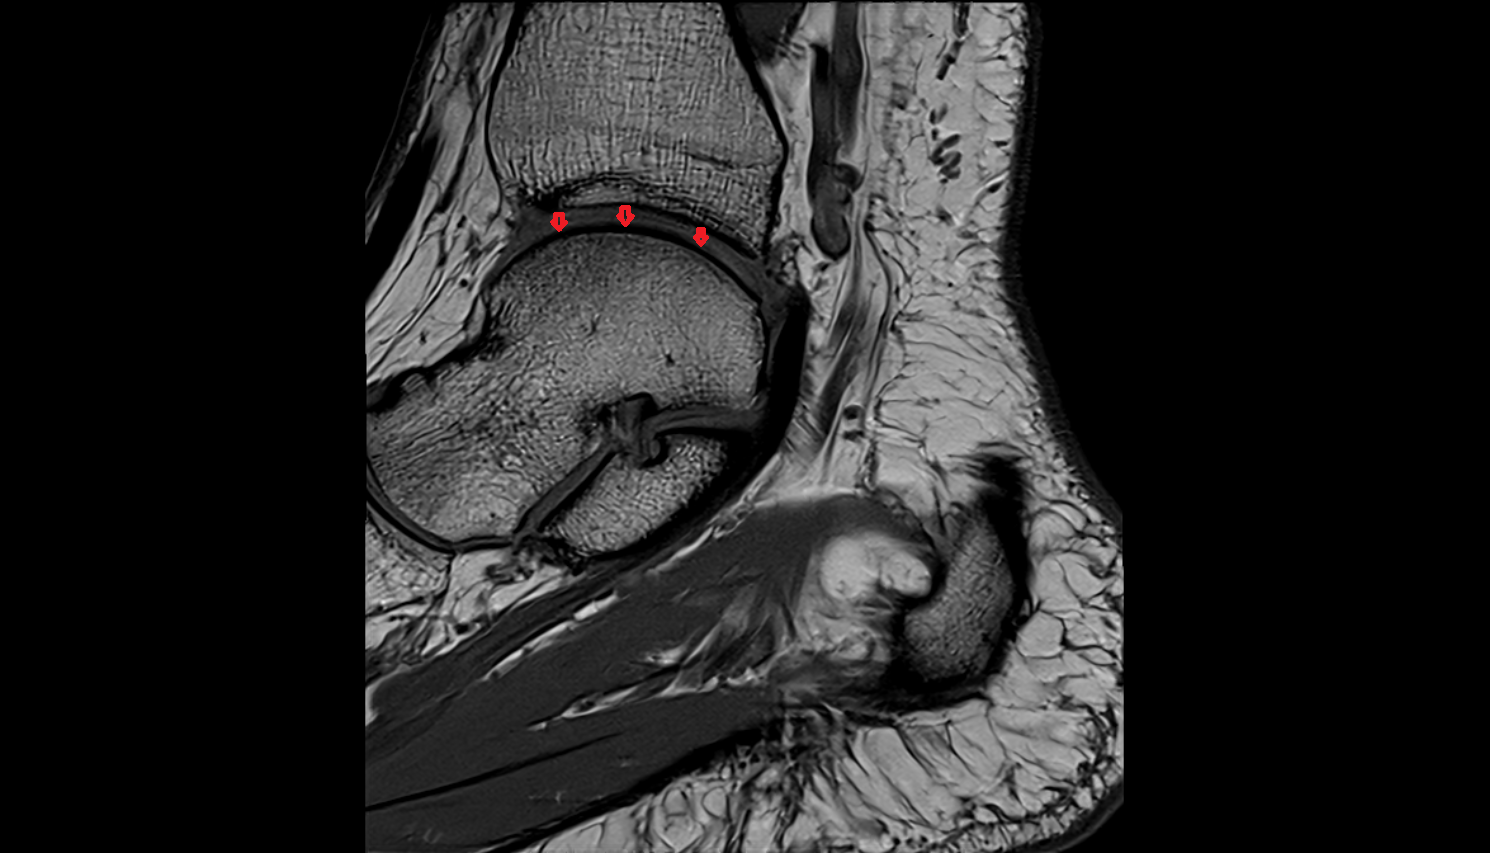

- Temporomandibular joint

- Articular disc of temporomandibular joint

- Articular eminence

- Mandibular condyle

- Mandibular fossa